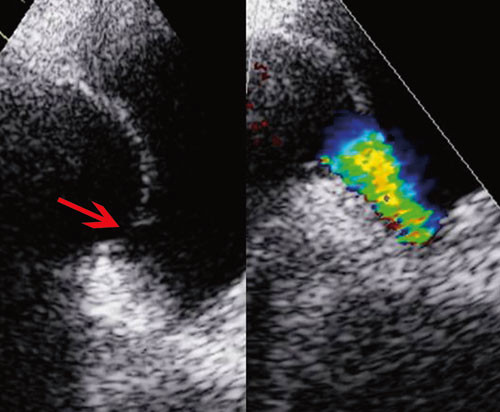

Siden hypoksemien kunne være utrykk for at blodet ble shuntet fra venøst til systemisk kretsløp, ble det injisert agitert saltvannsoppløsning (luftmikrobobler) i perifer vene. Umiddelbar påvisning av «kontrast» i venstre atrium antydet at det var en stor kontrastpassasje på forkammernivå (fig 1). En slik shunting av venøst blod til venstre hjertekammer kunne forklare pasientens hypoksemi og tungpust. For å kartlegge årsaksforholdene nærmere ble det utført transøsofageal ekkokardiografi da denne metoden gir høyere bildeoppløsning. Undersøkelsen avdekket et åpent (patent) foramen ovale (fig 2).

I en noe uortodoks projeksjon fremkom det at trikuspidalinsuffiensen var stor (grad 3 – 4/4). Trikuspidalklaffens seil var fortykket, korte og lite mobile. Klaffeseilene sto i halvåpen posisjon i systolen når de skulle være lukket. De påviste forandringene i trikuspidalapparatet ga mistanke om karsinoid hjertesykdom. Ved å plassere ultralydhodet under kostalbuen kunne leveren visualiseres. Leveren var inhomogen med multiple ekkotette lesjoner, slik at mistanken om karsinoid sykdom ble ytterligere forsterket (fig 3).